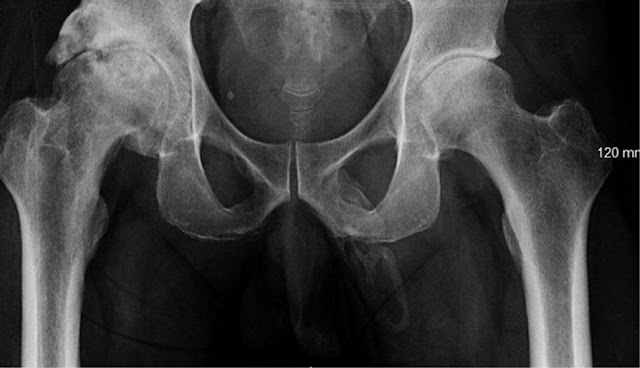

Georges El Hasbani of the American University of Beirut and his colleagues, explain the treatment of penis ossification in their case report, published in the journal Urology Case Reports. "The treatment of penis ossification depends on the extent of body ossification and the patient's symptoms."

The case involving an uncomfortable acute pain or mild chronic pain can be managed with oral analgesics, topical agents, intralesional injections, mechanical stretching or vacuum devices, and extracorporeal shock wave therapy. Serious cases of extreme chronic pain or erectile dysfunction are usually treated surgically," they added.